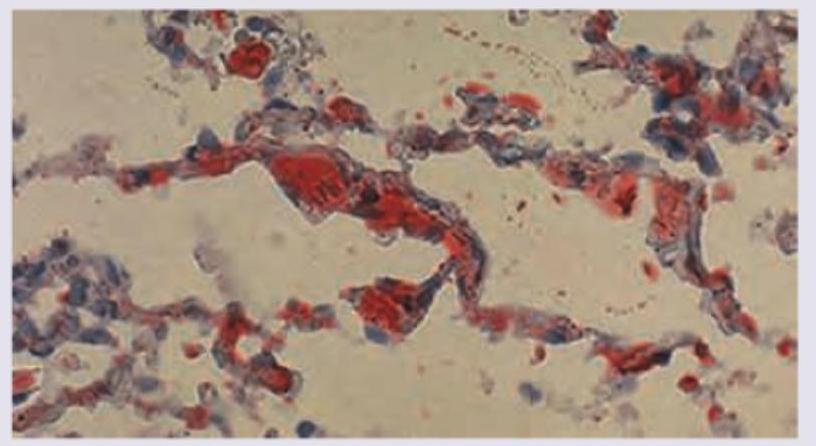

Postmortem lung specimen of a patient who developed severe respiratory distress and petechiae after fracture of shaft of femur is given below. All are true about the condition except:

Explanation: ***Diffuse white matter petechial hemorrhages*** - While **petechial hemorrhages** can occur in **fat embolism syndrome (FES)**, they are typically found in the **gray matter** and **white matter** of the brain, but the statement specifically mentions "diffuse white matter petechial hemorrhages" which is not the most characteristic or exclusive finding. - The most characteristic neurological finding in FES is **cerebral edema** and **microinfarcts** due to fat emboli, leading to altered mental status. *Oil Red O stain for fat* - **Oil Red O stain** is a crucial diagnostic tool used to identify **fat globules** in tissue sections, particularly in the lungs, confirming the presence of fat emboli. - This stain is used on **frozen sections** because routine paraffin embedding dissolves fat. *Noncardiogenic pulmonary edema* - **Fat embolism syndrome (FES)** [1] often leads to **acute respiratory distress syndrome (ARDS)**, which is characterized by **noncardiogenic pulmonary edema**. - This edema results from the inflammatory response triggered by fat emboli in the pulmonary capillaries, increasing vascular permeability. *GURD criteria* - The **Gurd and Wilson criteria** are clinical diagnostic criteria used to diagnose **fat embolism syndrome (FES)**. - These criteria include major signs (respiratory insufficiency, cerebral involvement, petechial rash) and minor signs (tachycardia, fever, retinal changes, fat in urine, etc.). **References:** [1] Cross SS. Underwood's Pathology: A Clinical Approach. 6th ed. (Basic Pathology) introduces the student to key general principles of pathology, both as a medical science and as a clinical activity with a vital role in patient care. Part 2 (Disease Mechanisms) provides fundamental knowledge about the cellular and molecular processes involved in diseases, providing the rationale for their treatment. Part 3 (Systematic Pathology) deals in detail with specific diseases, with emphasis on the clinically important aspects., pp. 146-147.